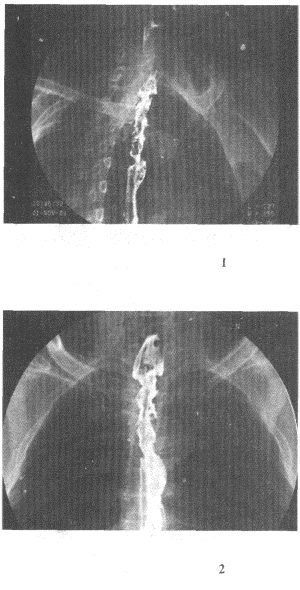

2.男,58歲,進食梗阻感,結合圖像,最可能的診斷為

正確答案:D 解題思路:食管范圍較長的不規則充盈缺損,管腔變窄,伴表面有龕影,結合病史為食管癌性病變。

3.男,38歲,鋇劑示食管壁張力減低,蠕動減弱,鋇劑排空延遲,并見食管下段有串珠狀充盈缺損影,首先應考慮

正確答案:A 解題思路:食管的串珠狀充盈缺損影為食管靜脈曲張的典型表現。